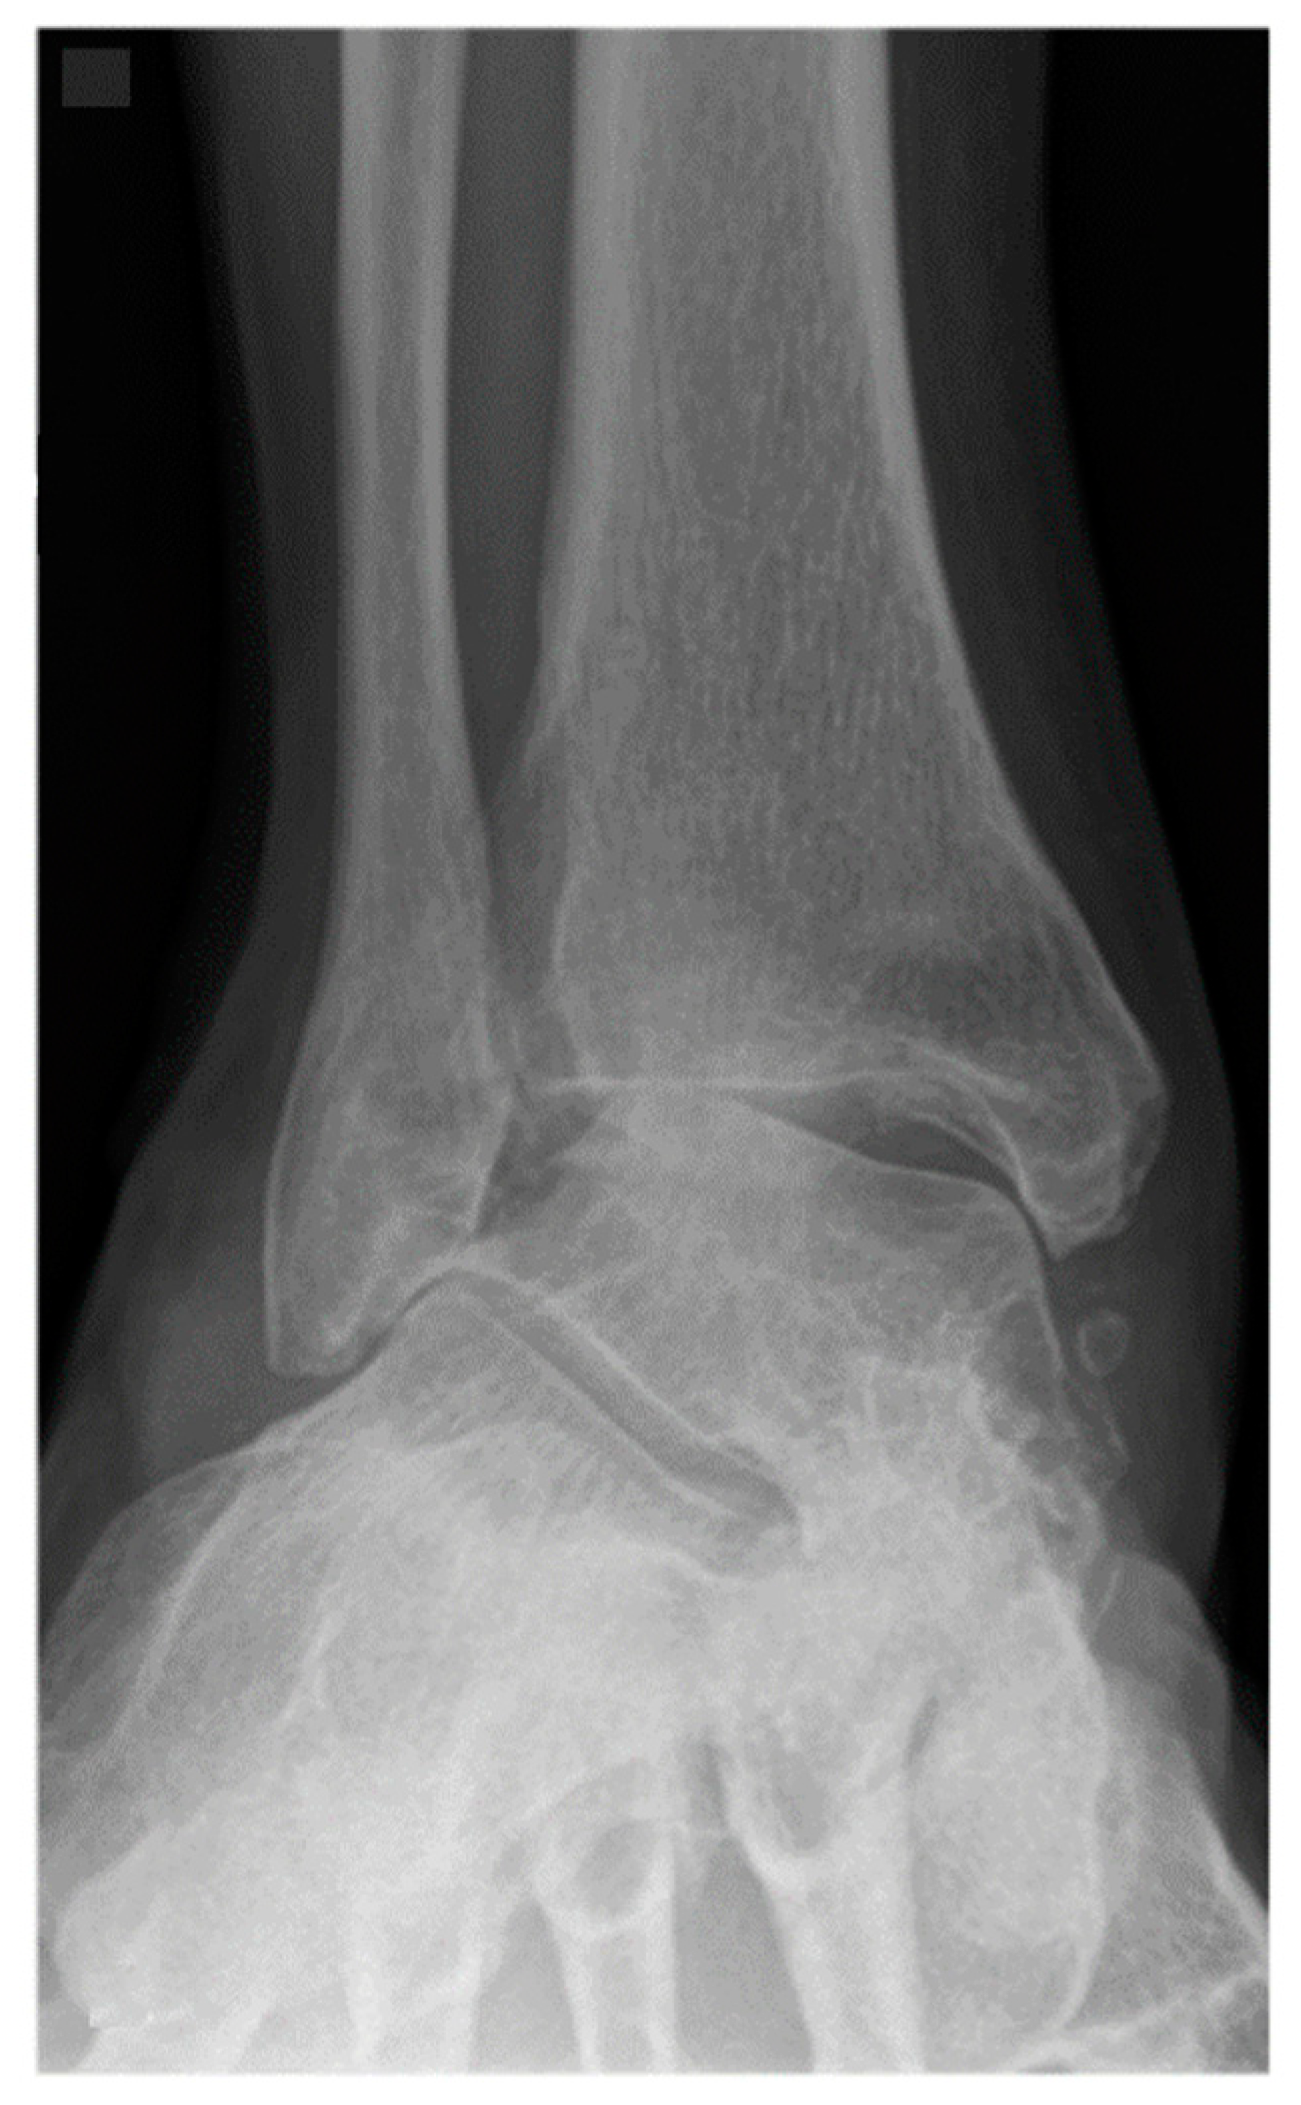

Figure 2.

A 62-year-old female patient presenting end-stage valgus tibiotalar osteoarthritis.